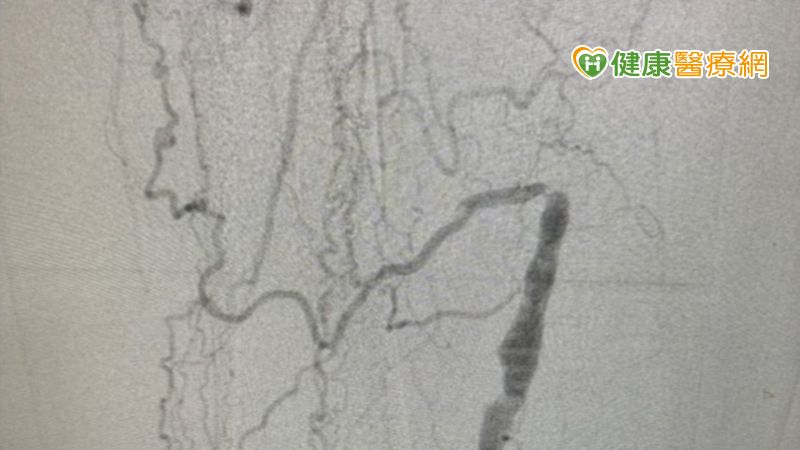

▲患者因下肢動脈血管阻塞,血液代償性繞道由較小的血管通過,造成血流比一般人小,會出現腿部無力、麻、冷或是間歇性跛足等症狀。

雖然塗藥支架是治療周邊動脈阻塞的首選,但臨床的狀況可能不會那麼單純,朱醫師補充說道,與心血管阻塞不同,周邊動脈阻塞的血管阻塞長度、複雜度往往都比心臟複雜許多。有的病患血管阻塞了二三十公分(心臟約為2-3公分),有的病患一條血管分成好幾段阻塞,有的甚至是一條腿阻塞了好幾條血管。這時就需要仰賴專業醫師來規劃治療的策略,有些病患只需要使用塗藥氣球就有很好的治療效果,但有些嚴重的病患會需要塗藥支架去支撐血管,有些病患更是前段用塗藥支架、後段用塗藥氣球的複合方式,去治療長度較長的阻塞。